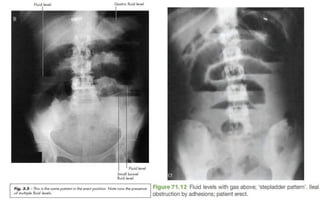

• Erect abdominal films are no longer routinely obtained and the

radiological diagnosis is based on a supine abdominal film.

• An erect film may subsequently be requested when further doubt exists.

• In intestinal obstruction, fluid levels appear later than gas shadows as it

takes time for gas and fluid to separate (most prominent on an erect film).

• In adults, two inconstant fluid levels, one at the duodenal cap and the

other in the terminal ileum, may be regarded as normal.

• In infants a few fluid levels in the small bowel may be physiological.